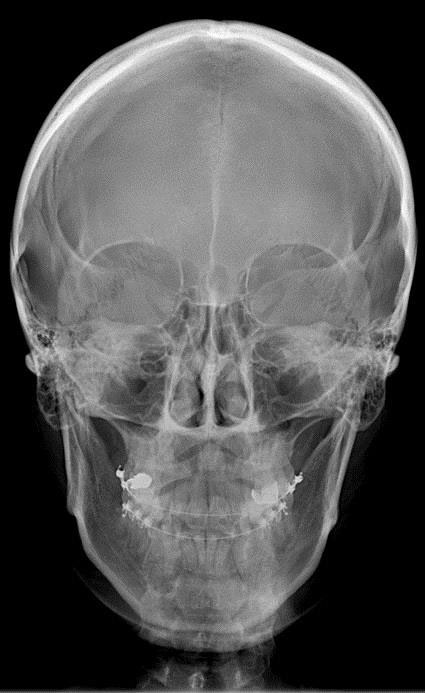

Profesjonalne, bezpieczne badania radiologiczne dla precyzyjnej diagnostyki wad zgryzu oraz stworzenia planu leczenia dopasowanego do potrzeb pacjenta

Ortodoncja posiada własną nowoczesną pracownię rentgenowską, w której bezpiecznie i szybko wykwalifikowany i doświadczony personel wykona wysokiej jakości niezbędne do diagnostyki i planowania badania radiologiczne.

Dobra diagnostyka i diagnoza wykonania na jej podstawie jest warunkiem powstania dobrego planu leczenia.

Aparat ten pozwala na uzyskanie precyzyjnych obrazów 2D dzięki funkcji multilayer i technologii wiązki RTG w kształcie litery V. Badanie może być wykonane w 4 rozdzielczościach obrazu w trybie 3D. Posiada funkcję redukcji artefaktów z metalowych elementów. Ma również 5 wielkości pól obrazowania.